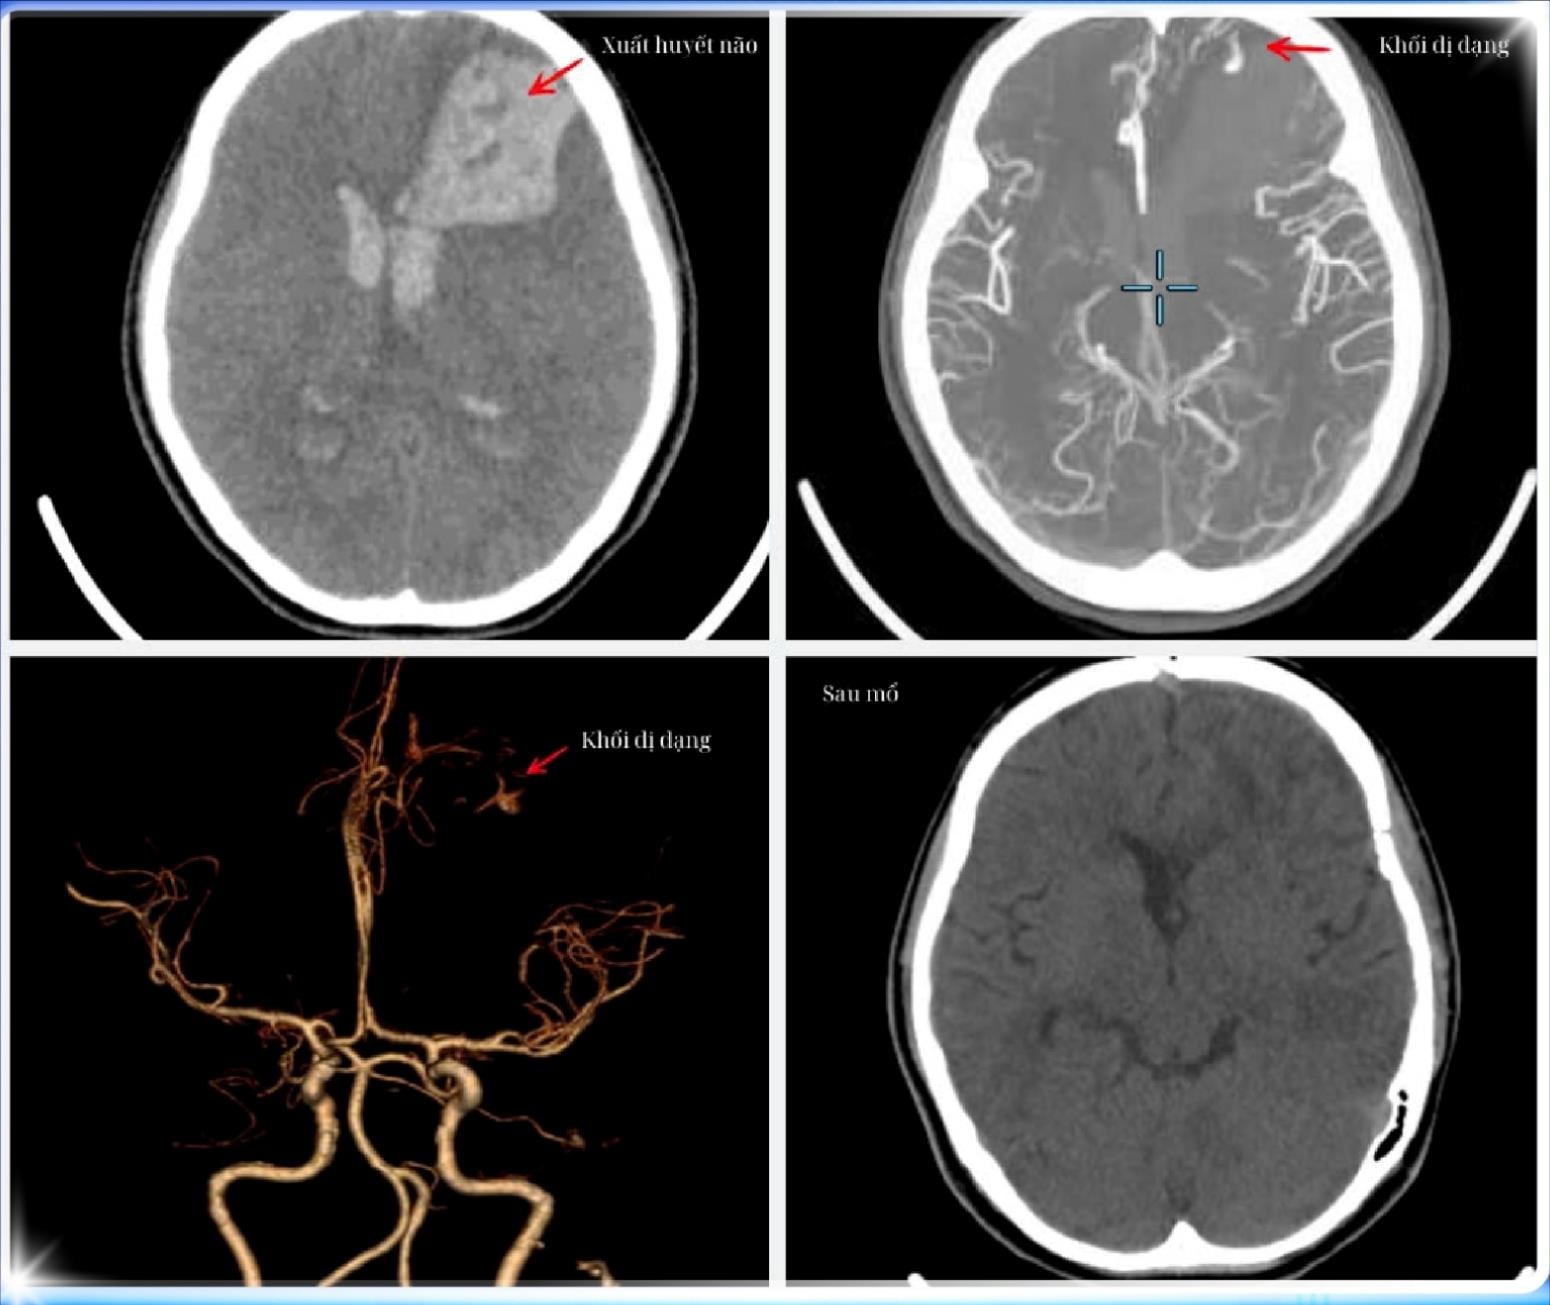

Kết quả chụp MSCT mạch máu não cho thấy người bệnh có tình trạng xuất huyết não vùng trán trái do vỡ dị dạng động tĩnh mạch não, máu đã tràn vào não thất, đường giữa bị đẩy lệch nguy hiểm 10mm, não thất giãn cấp tính.

Các bác sĩ quyết định mổ khẩn cấp để bảo đảm an toàn, giảm thiểu biến chứng cho nữ sinh. Ảnh: BVCC

Hình ảnh phim chụp khối dị dạng mạch máu não. Ảnh: BVCC